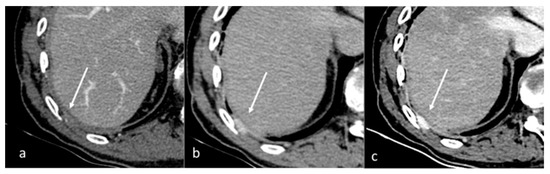

| Si-Mohamed et al. [67] Retrospective study | France | To assess whether VNC images derived from contrast dual-layer DECT images could replace TNC images for aortic intramural hematoma diagnosis in acute aortic syndrome imaging protocols by performing quantitative as well as qualitative phantom and clinical studies. | 21 | IQon, Philips Healthcare No C.I. | Dual-layer -DECT offers similar performances with VNC and TNC images for intramural hematoma diagnosis without compromise in diagnostic image quality. VNC imaging with dual-layer DECT reduces the number of acquisitions and radiation exposure in acute aortic syndrome imaging protocol. |